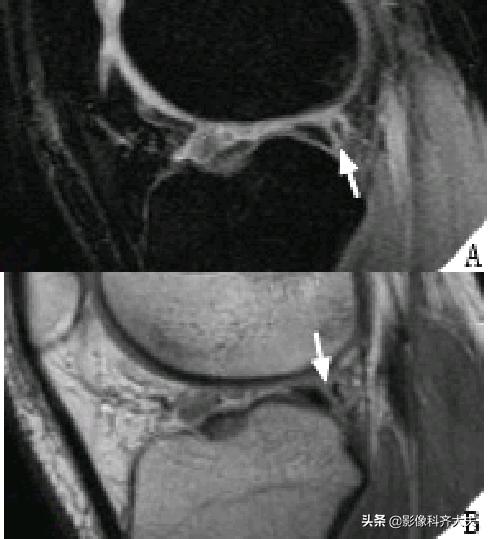

瓣状撕裂

桶柄状撕裂示意图

半月板撕裂后移位